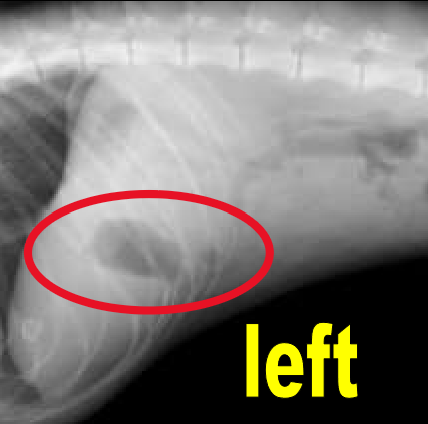

Serosal Detail

contrast between abdominal organs and the ability to see their edges

Border effacement

2 structures of the same opacity are in contact, so their margins cannot be distinguished